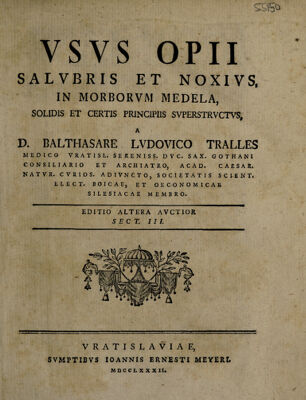

Usus opii salubris et noxius, in morborum medela ... / [Balthasar Ludwig Tralles].

- Balthasar Ludwig Tralles

- Date:

- 1774-1782

Licence: Public Domain Mark

Credit: Usus opii salubris et noxius, in morborum medela ... / [Balthasar Ludwig Tralles]. Source: Wellcome Collection.